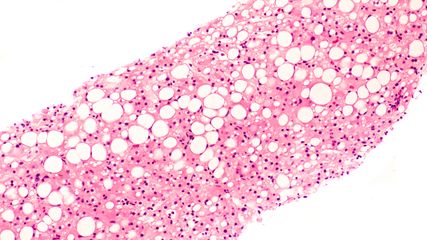

In der Indikation metabolisch bedingte Lebersteatose bzw. Steatohepatitis scheiterten über viele Jahre zahlreiche Therapieversuche. Seit Kurzem stehen erstmals wirksame und zugelassene Therapien zur Verfügung. Als effektiv erwiesen haben sich Substanzen aus der Gruppe der GLP-1-Rezeptor-Agonisten sowie Resmetirom, ein selektiver Agonist am Schilddrüsenhormonrezeptor β.

Die Arbeitsdiagnose einer MASLD (mit metabolischer Dysfunktion assoziierte steatotische Lebererkrankung – bis vor Kurzem als NAFLD bezeichnet) ist einfach: Wird mittels Bildgebung, in der Regel Ultraschall oder Biopsie, eine Steatose der Leber festgestellt und liegen kardiometabolische Risikofaktoren, jedoch kein hoher Alkoholkonsum vor, so kann von einer MASLD ausgegangen werden. Kommen Inflammation und möglicherweise Fibrose hinzu, so spricht man von MASH (mit metabolischer Dysfunktion assoziierte Steatohepatitis). Bei 80% der Betroffenen bleibt es bei einer Steatose mit allenfalls minimalem Progressionsrisiko, erläuterte Univ.-Prof. Dr. Herbert Tilg, Leiter der Innsbrucker Universitätsklinik für Innere Medizin I. In 20% der Fälle liegt jedoch eine MASH vor, die mit einem beträchtlichen Risiko für Progression zu Zirrhose und Dekompensation sowie mit einer erhöhten Inzidenz von Leberkarzinomen assoziiert ist. In dieser Patientengruppe ist die Mortalität signifikant erhöht, wobei kardiovaskuläre Todesursachen die größte Rolle spielen. Daher besteht erheblicher Bedarf an wirksamen Therapien, so Tilg, der ergänzte, dass man bis heute nicht vollständig verstehe, warum es bei der Mehrheit der Betroffenen bei MASLD bleibt, während ein Teil eine MASH entwickelt. Dabei dürften extrahepatische Signale, unter anderem aus dem Fettgewebe, aber auch bakterielle Stoffwechselprodukte aus dem Darmmikrobiom eine wichtige Rolle spielen.1

In einer Phase-III-Studie mit knapp tausend Patienten wurde mit Resmetirom über 52 Wochen bei 25,9% der mit 80mg und bei 29,9% der mit 100mg behandelten Patienten eine Senkung des NAFLD-Activity-Scores (NAS) um mindestens zwei Punkte ohne Verschlechterung der Fibrose beobachtet (Abb. 1A). Bei 24,2% (80mg) und 25,9% (100mg) der Patienten konnte eine Reduktion der Fibrose ohne Verschlechterung des NAS erreicht werden (Abb. 1B). Resmetirom erwies sich im Vergleich zu Placebo als signifikant überlegen. Zusätzlich kam es in den Verumgruppen zu einer signifikanten Senkung des LDL-Cholesterins zu Woche 24 (Abb. 1C).7 Tilg: „Wir beginnen zu verstehen, welche Bedeutung die Schilddrüse für die Leber hat.“

Abb. 1: Ergebnisse der Phase-II-Studie zu Resmetirom bei MASH. A: Senkung des NAFLD-Activity-Scores (NAS) um mindestens zwei Punkte ohne Verschlechterung der Fibrose zu Woche 52. B: Reduktion der Fibrose ohne Verschlechterung des NAS zu Woche 52. C: prozentuelle Veränderung des LDL-Cholesterins zu Woche 24 (modifiziert nach Harrison SA et al. 2024)7